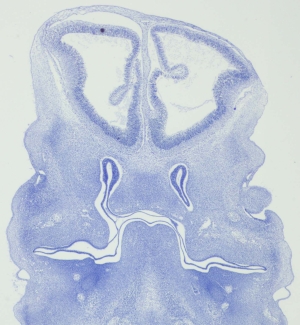

Stage 18

CfS 18

d31-35